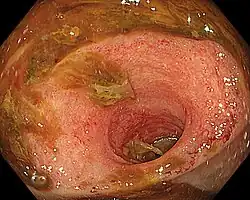

| Ileitis caused by capecitabine. | |